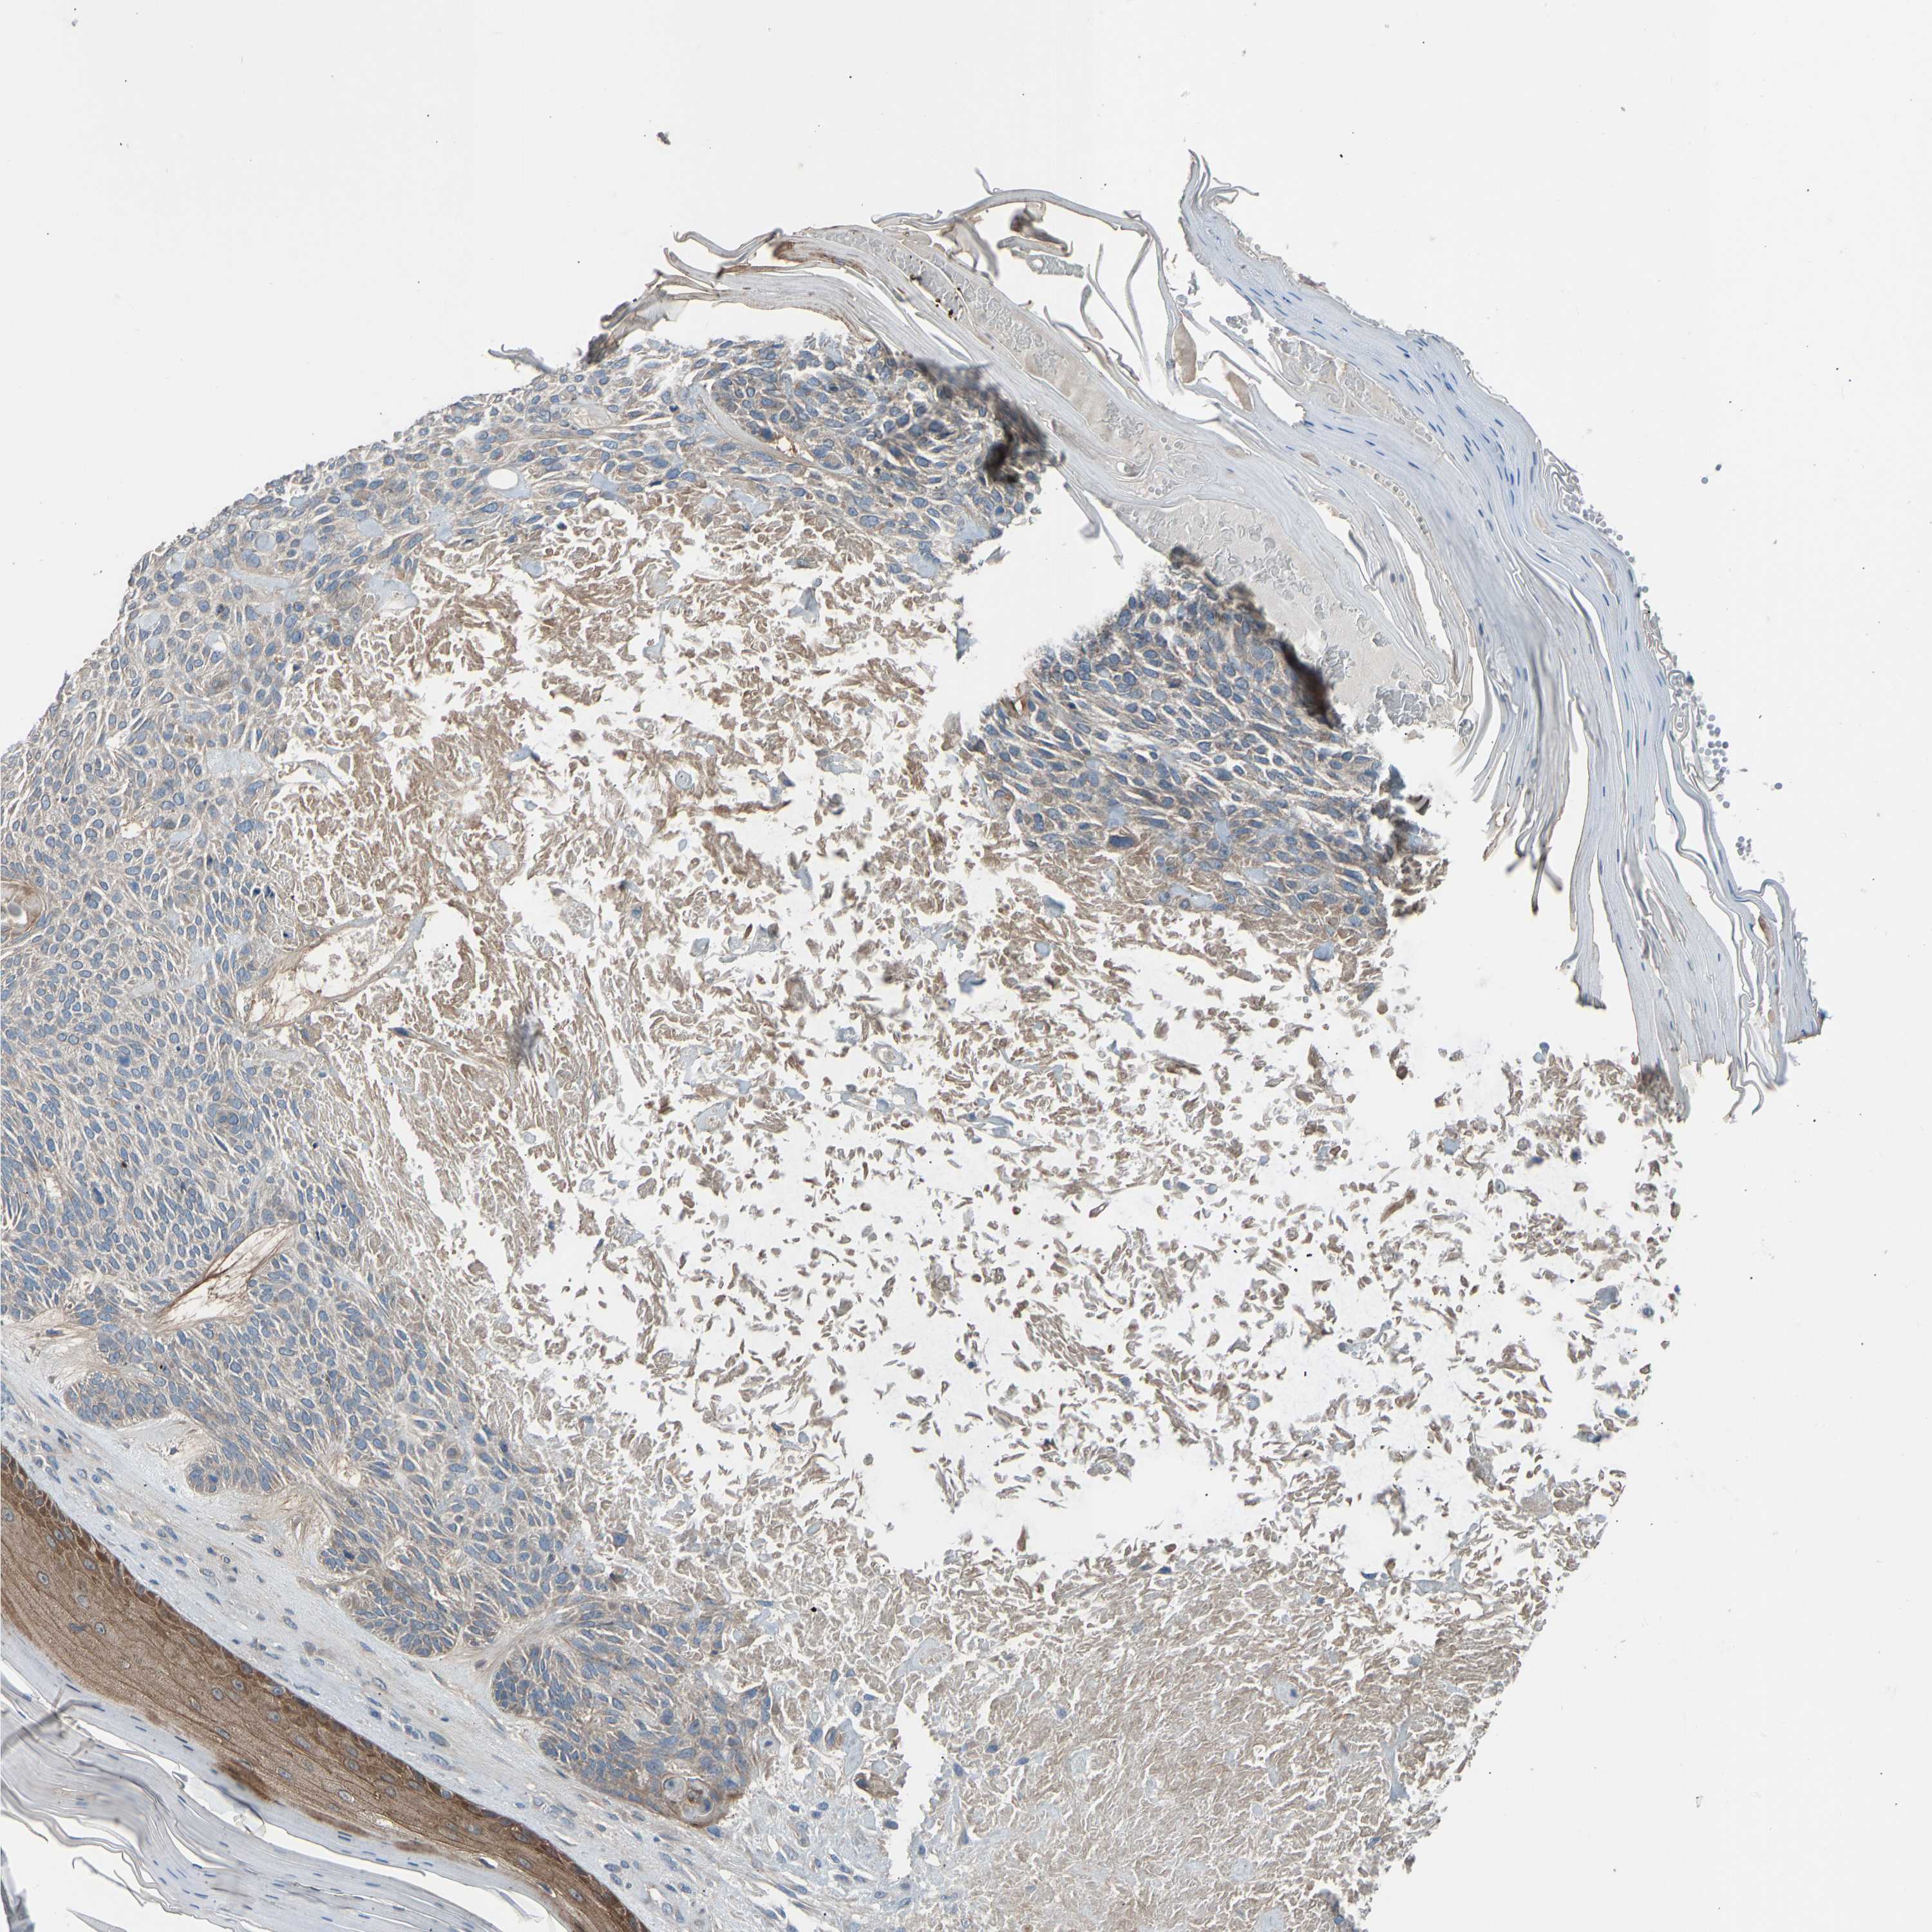

SKIN CANCER - Protein expressioni

A mouse-over function shows sample information and annotation data. Click on an image to view it in a full screen mode. Samples can be filtered based on level of antibody staining by selecting one or several of the following categories: high, medium, low and not detected. The assay and annotation is described here.

Antibody stainingi

Antibody staining in the annotated cell types in the current human tissue is reported as not detected, low, medium, or high, based on conventional immunohistochemistry profiling in selected tissues. This score is based on the combination of the staining intensity and fraction of stained cells.

Each image is clickable and will lead to virtual microscopy that enables deeper exploration of all samples and also displays staining intensity scores, fraction scores and subcellular localization as well as patient and tissue information for each sample.

Antibody CAB018971

Basal cell carcinoma

Squamous cell carcinoma in situ, NOS

Squamous cell carcinoma, NOS